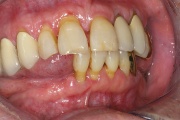

Sjörgeni sündroomist tingitud suukuivus